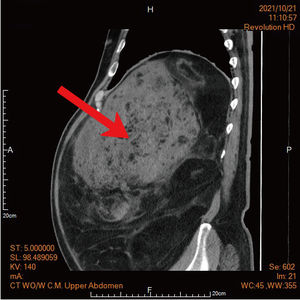

68歲的楊先生,身材高大壯碩,曾經因為心肌梗塞就醫後撿回一命,之後便積極減重,五年下來四肢都瘦了,肚子卻瘦不下來,進一步就一檢查,發現肚子裡竟不是脂肪,而是重達22公斤的巨大腫瘤,就連肝臟及腸胃道都因腫瘤推擠而挪到腹腔左側,最後由馬偕醫院團隊收治,結合跨外科團隊最後才順利摘除。 《詳全文...》